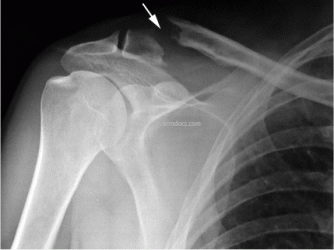

b. Appearance after fixation with fibretape and dogbones.